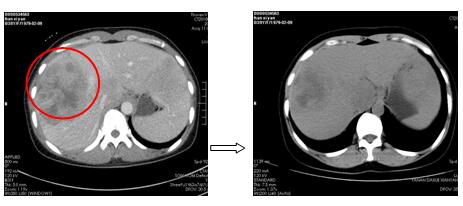

我科現(xiàn)有經(jīng)驗(yàn)豐富、專(zhuān)業(yè)的腫瘤介入醫(yī)生,可開(kāi)展肝癌經(jīng)肝動(dòng)脈灌注化療栓塞術(shù)(TACE)等各類(lèi)介入手術(shù),開(kāi)科以來(lái),已成功完成介入術(shù)2例,術(shù)后創(chuàng)傷小、恢復(fù)快、并發(fā)癥小、療效顯著,收到了開(kāi)科以來(lái)的第一封感謝信。

圖3.肝癌介入術(shù)